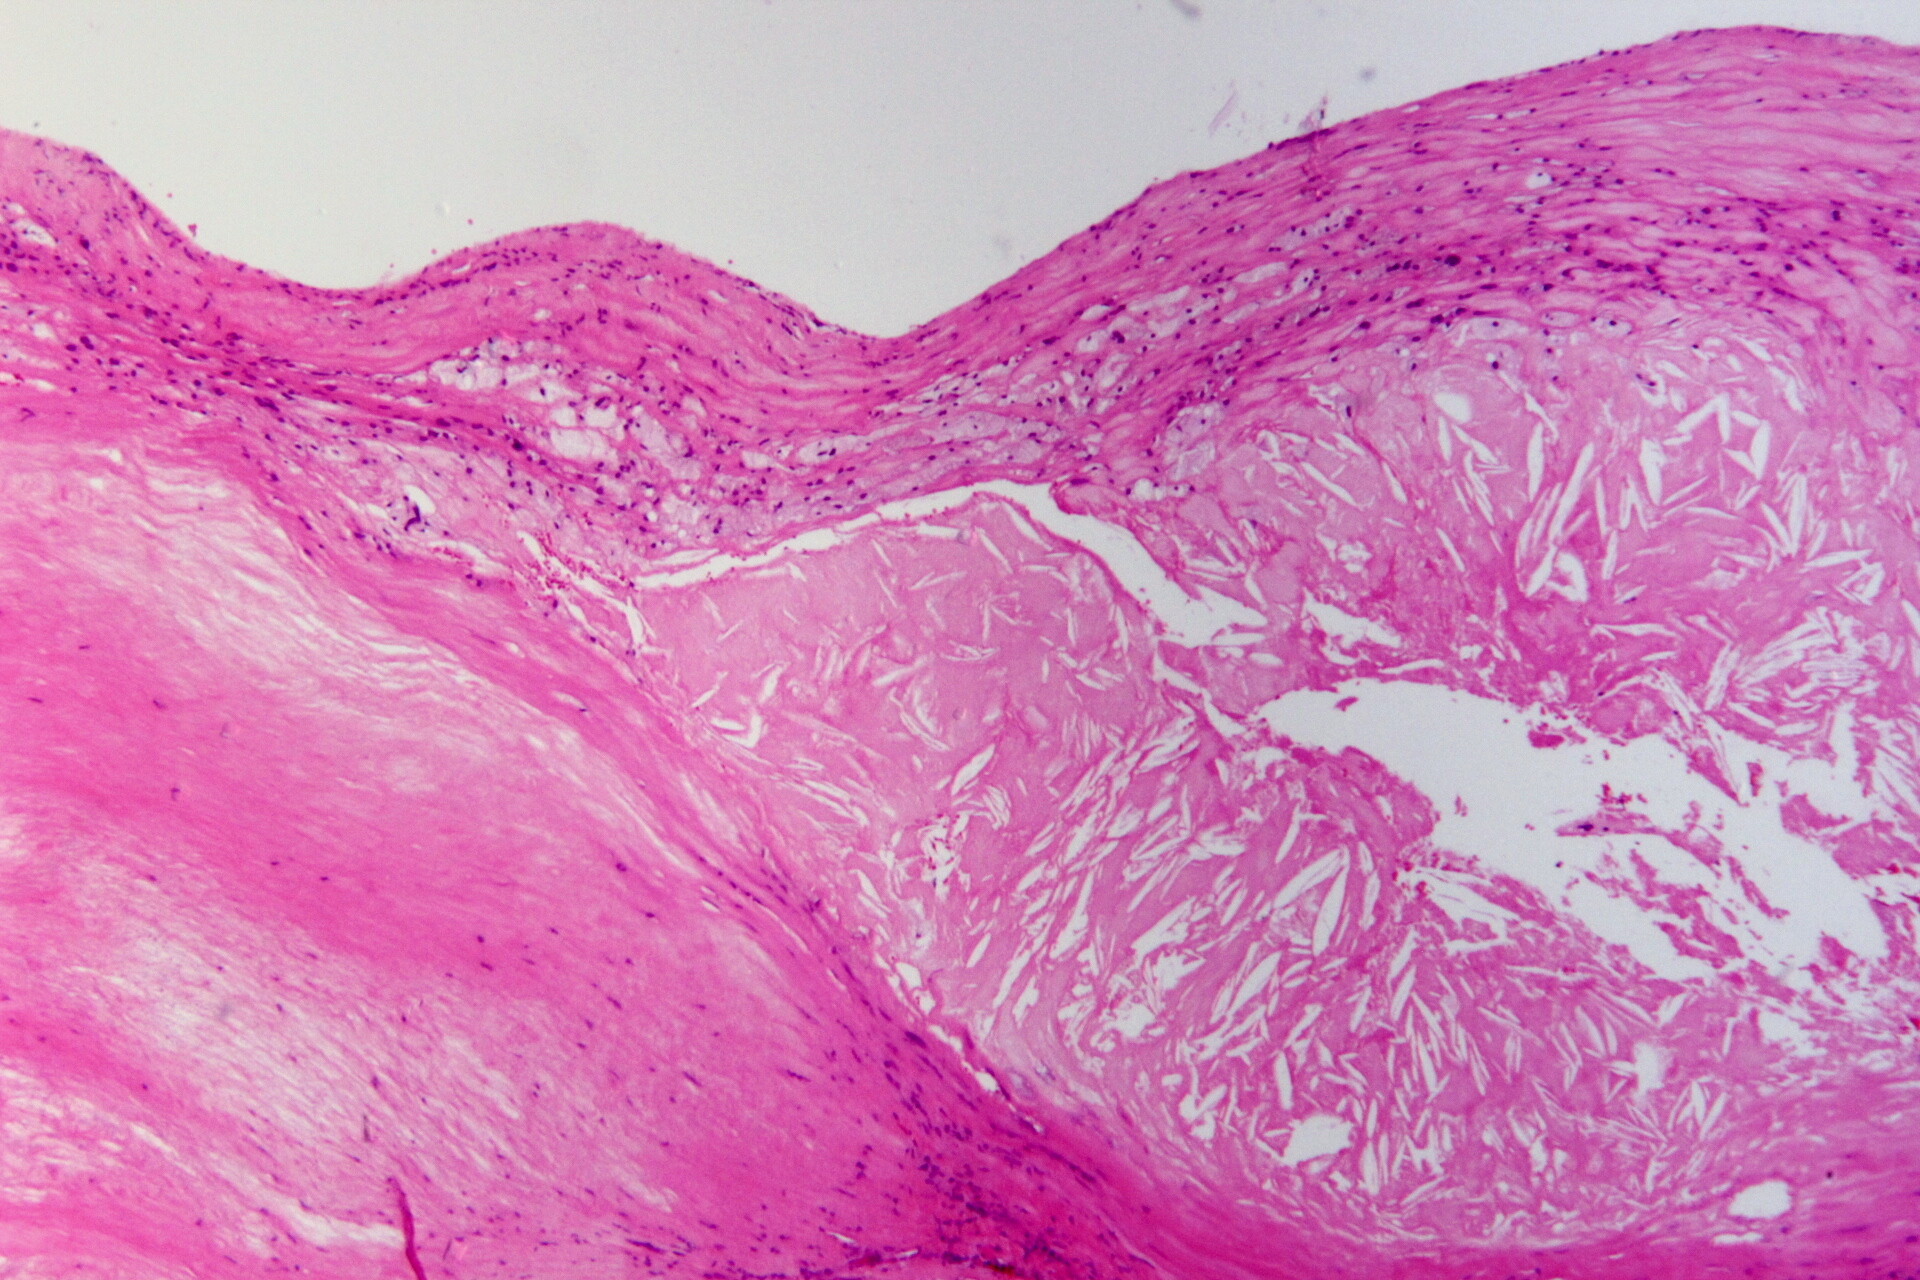

Atherosklerotischer Plaque mit Cholesterinkristalllücken, Schaumzellen und Fibrose. © By Pathoa via Wikimedia Commons

Start Atherosclerosis©By Patho (Own work) [CC BY-SA 3.0 (http-::creativecommons.org:licenses:by-sa:3.0)], via Wikimedia Commons Atherosclerosis©By Patho (Own work) [CC BY-SA 3.0 (http-::creativecommons.org:licenses:by-sa:3.0)], via Wikimedia Commons